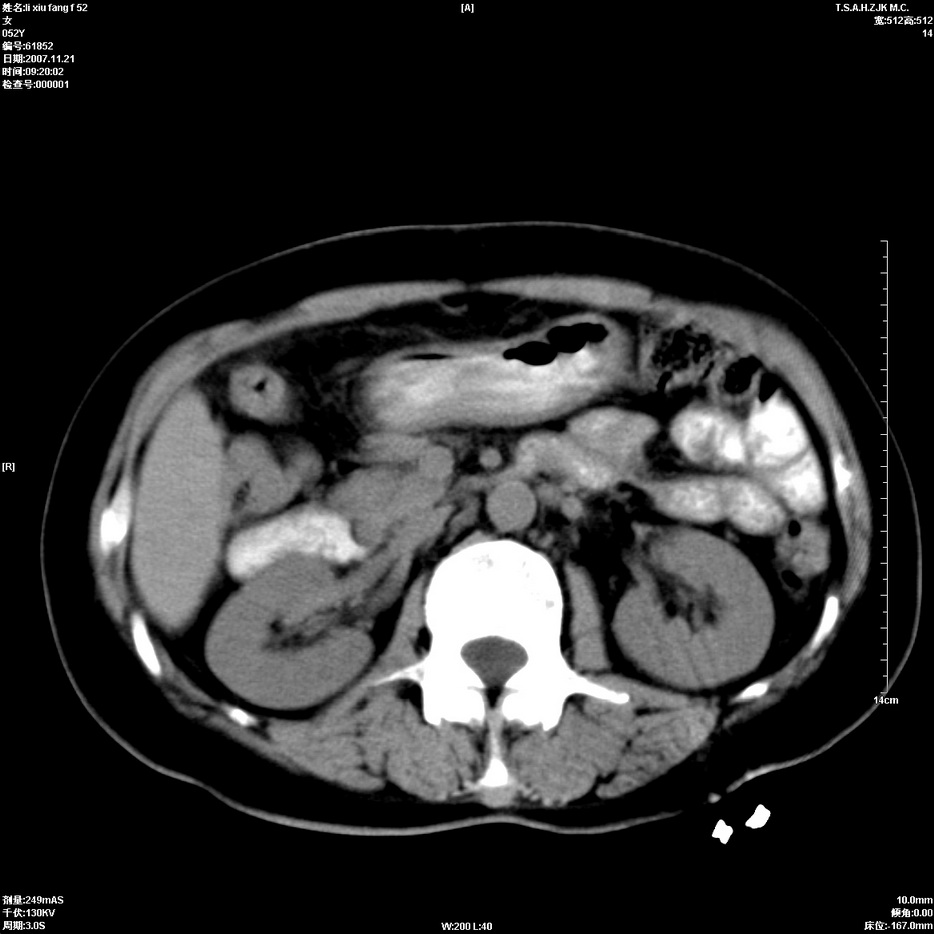

标题: CT12858:女,52岁,胎甲球蛋白861肝左叶占位,肝癌。下腔静 [打印本页]

标题: CT12858:女,52岁,胎甲球蛋白861肝左叶占位,肝癌。下腔静

肝左叶巨大低密度灶肿块,增强符合快进快出表现,有动静脉交通支;静脉期,下腔静脉内有充盈缺损,afp明显升高,支持肝癌并下腔静脉癌栓形成。

支持楼主   门静脉主干及左支癌栓形成

以下是引用拾荒者在2008-4-15 22:57:00的发言:[br]肝左叶巨大低密度灶肿块,增强符合快进快出表现,有动静脉交通支;静脉期,下腔静脉内有充盈缺损,afp明显升高,支持肝癌并下腔静脉癌栓形成。